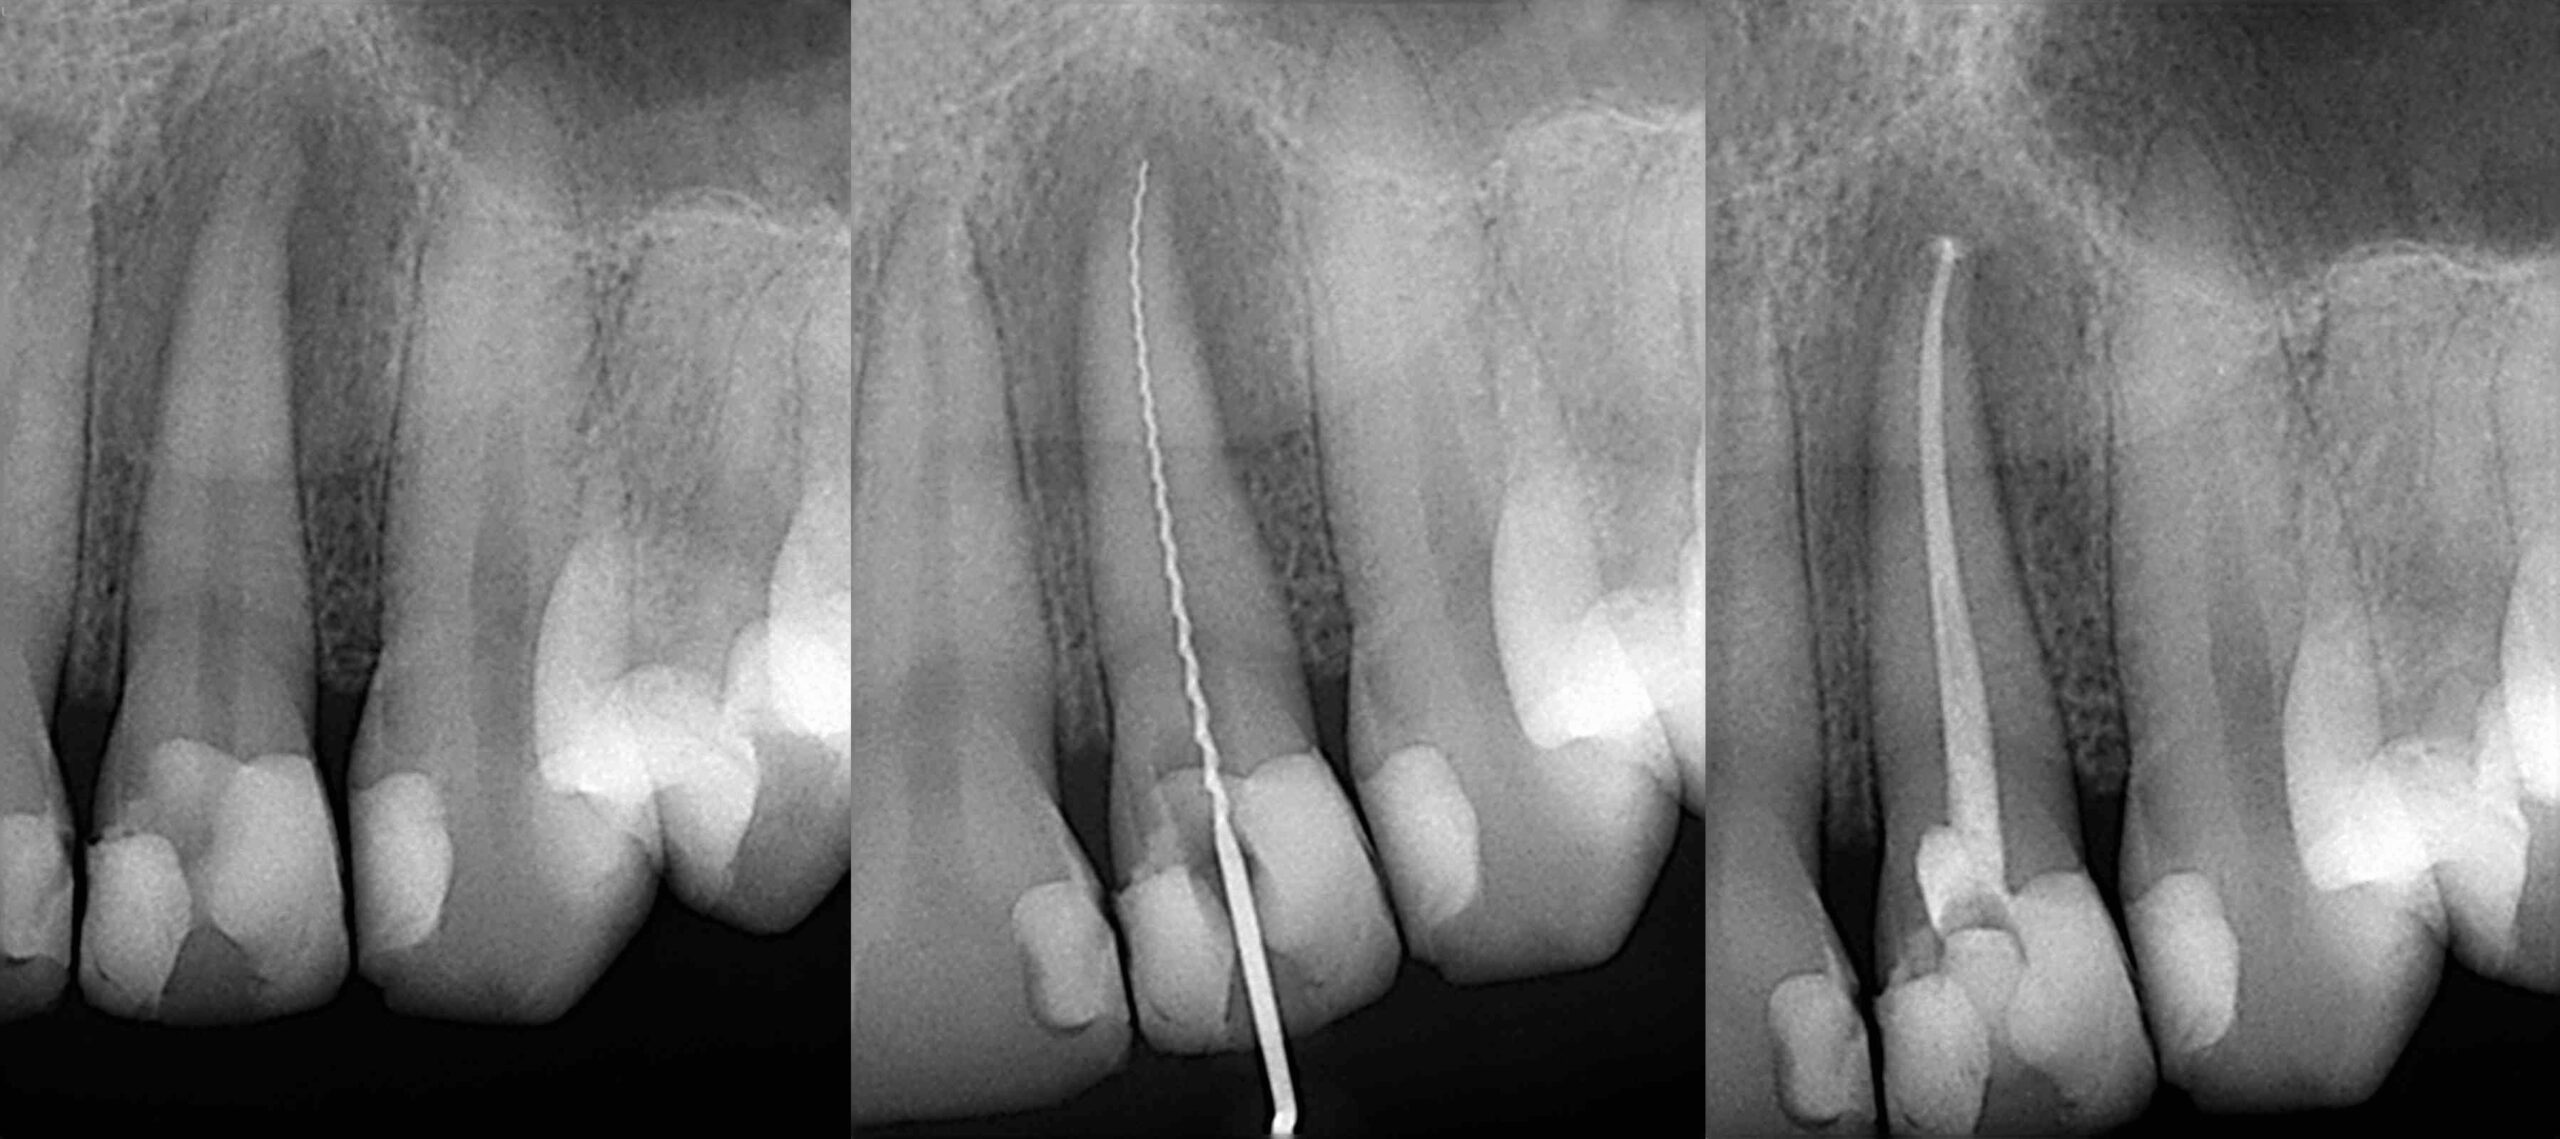

If you have tooth pain or are showing other signs of infection, we examine your mouth to ensure that root canal treatment is the best solution for you. We take digital x-rays to look at the root canals in your tooth in more detail and aid our diagnosis and planning. We also make sure the infection hasn’t spread to any other areas. We make sure you are feeling comfortable with the treatment process and give you the chance to ask us any questions.

We clean the root canals with an antibacterial solution and use special tiny instruments to shape them effectively. We fill the canals with a rubber material known as gutta-percha to seal them and prevent re-infection.

During a root canal, the infected tissues are removed and your tooth is flushed with an antibacterial solution to clean it effectively. Your tooth is then shaped, filled and sealed to restore function and to prevent reinfection.